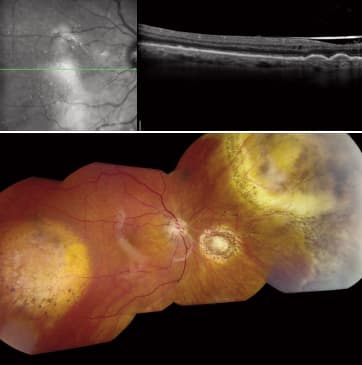

Figures 1 and 1a. Malignant posterior uveal melanoma of the left eye in a 75-year-old Hispanic female.

Figure 2. Eighteen months after successful brachytherapy, the patient's left eye developed radiation retinopathy, which was treated over the course of 24 months with intravitreal bevacizumab. Vision stabilized at 20/50; however, a complex and progressive hemorrhagic retinal detachment developed.

Figures 3 and 3a. The patient's left eye following a single combined 23-gauge procedure for cataract and repair of a complex retinal detachment. Prior to surgery a favorable response to brachytherapy for malignant uveal melanoma had been documented over a 4-year period.

The patient is a 75-year-old Hispanic female with malignant posterior uveal melanoma of the left eye. In May 2006, with visual acuity of 5/200, she was treated with iodine-125 plaque brachytherapy. Over the next 12 months, the tumor regressed and vision improved to 20/40. Eighteen months after brachytherapy, the eye developed radiation retinopathy, which was treated over the course of 24 months with intravitreal bevacizumab. Vision stabilized at 20/50; however, likely due to the retinopathy, a complex hemorrhagic retinal detachment as well as a visually significant cataract emerged. The retinal detachment was progressive, and the patient experienced a significant decline in visual acuity.

Since the patient's melanoma had an excellent response to brachytherapy that was documented over a 4-year period, we were able to consider surgical repair of the complex retinal detachment to restore the ocular anatomy and vision. Because the cataract was contributing to visual acuity loss and would confound the posterior segment repair, we elected to perform a single combined procedure. After we confirmed the tumor was involuted and saw no evidence of active melanoma on exam, imaging or ultrasound, we scheduled surgery.